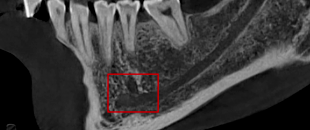

(1)多生牙的定位:

口腔ct怎么拍摄【专科天地】没有口腔CT,你根本不会想到自己的牙齿长得多“奇葩”!_https://www.jmylbn.com_新闻资讯_第14张